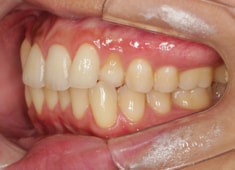

治療前